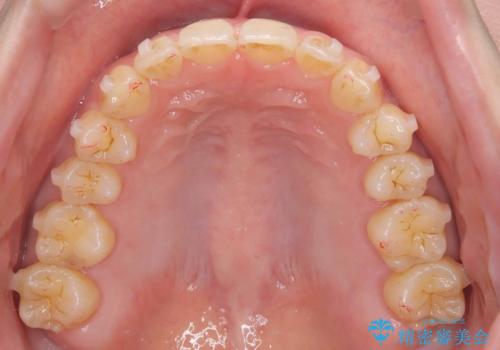

- 「下の前歯が斜めになっている」を主訴に来院された患者様です。

下顎前歯に叢生があり、右上2は反対咬合の状態でした。

抜歯は行わずインビザラインで治療を行いました。